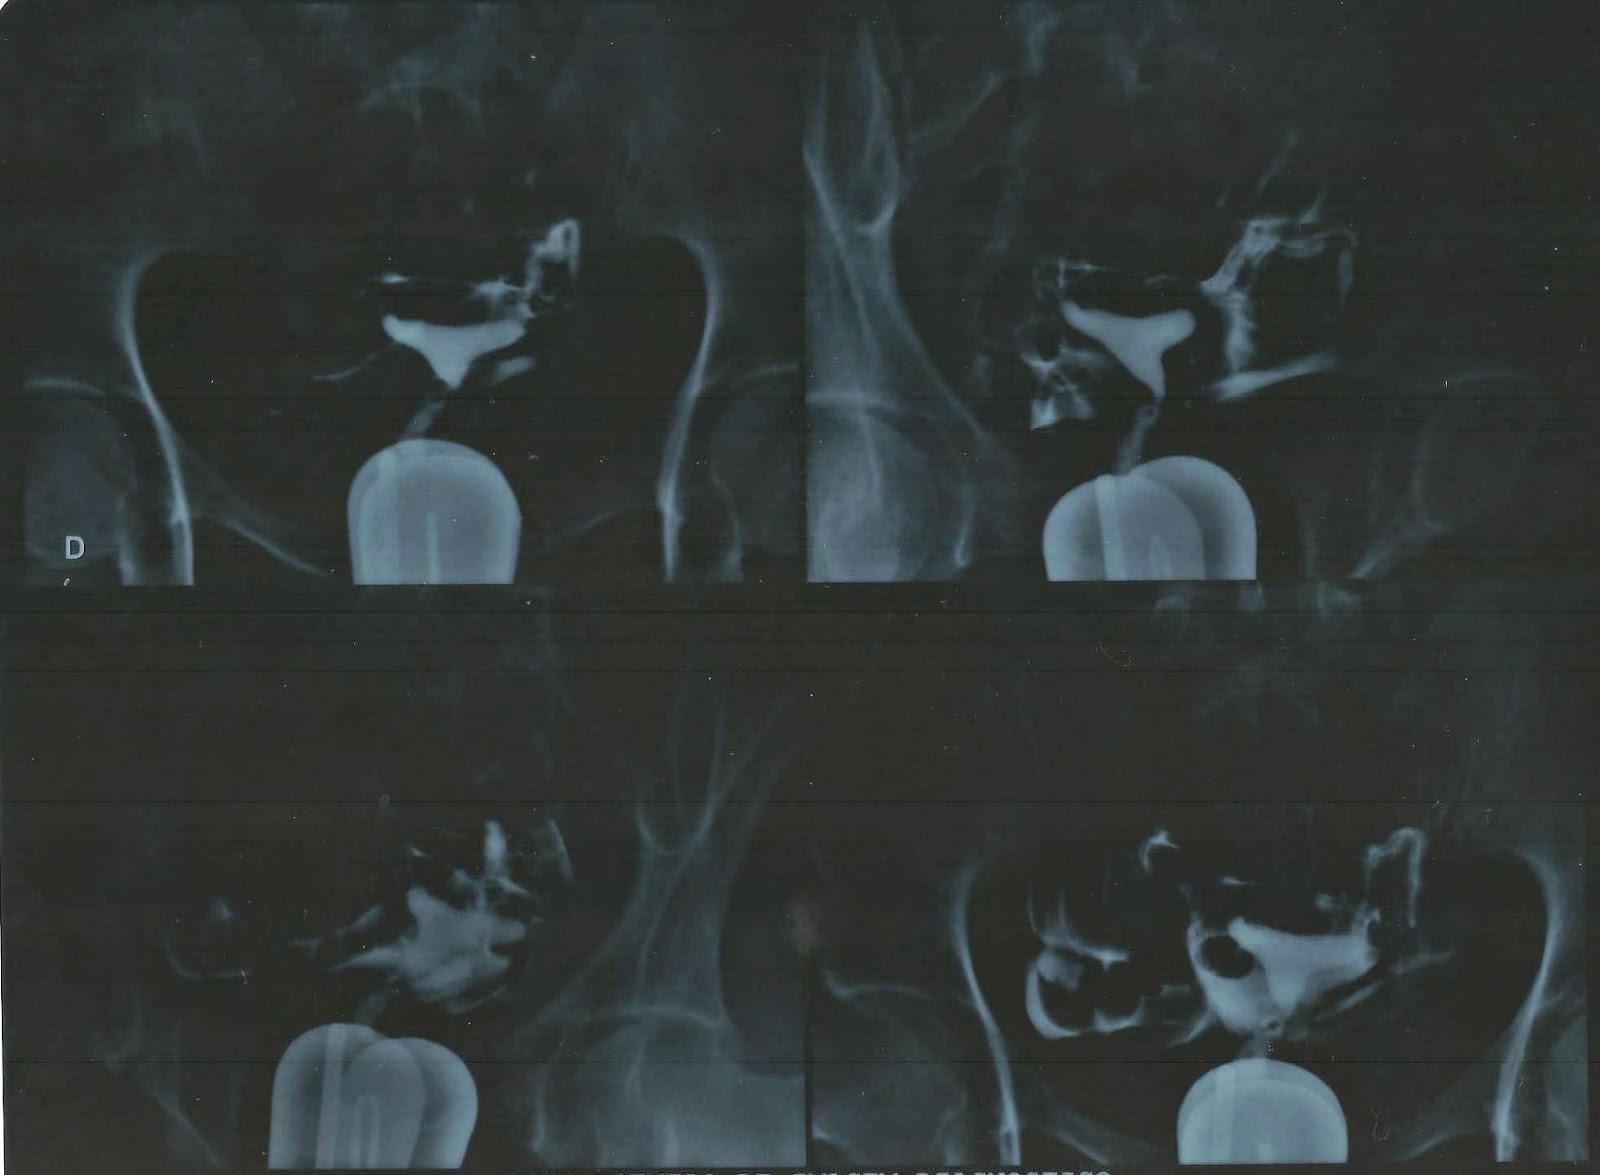

A

histerossalpingografia nada mais é do que um raio-x da cavidade uterina e das

trompas, realizado com a injeção de

contraste por meio do colo do útero, com o auxílio de uma sonda. Simples assim.